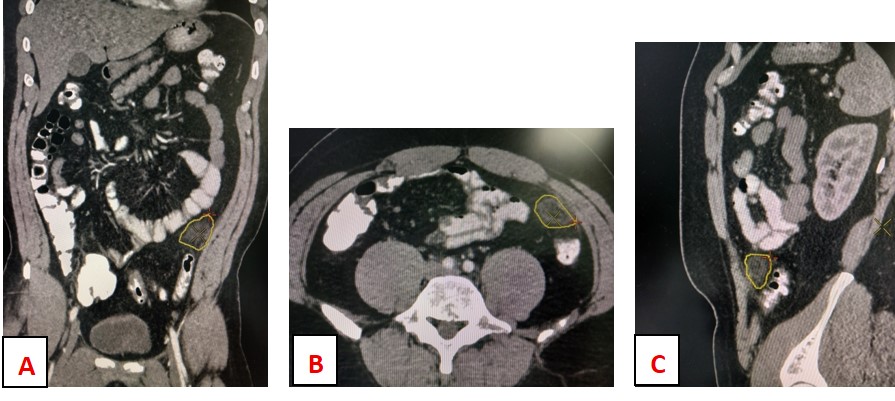

Mesenteric panniculitis: A case report.

Adeyinka Adejumo, Babatunde E. Osobu, Olusola O. Akanbi, Abiola M. Adejumo

223-227